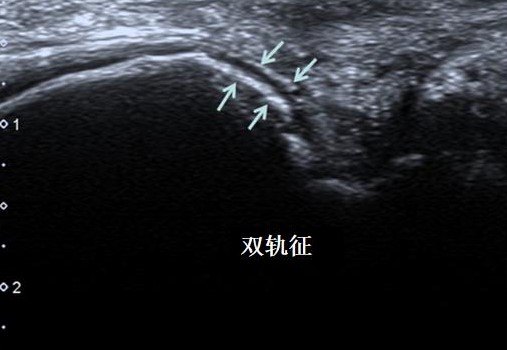

双轨征

超声检查发现"双轨征","痛风石"是诊断痛风特异性较高的特征.